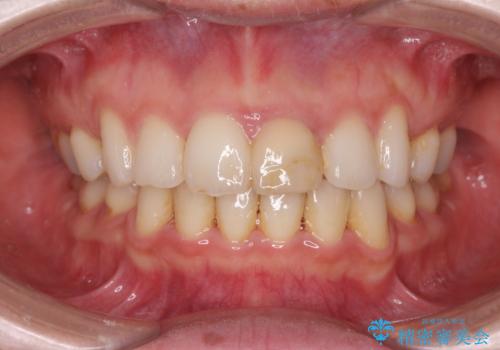

変色してきた前歯をセラミック治療

- 神経の治療をしたまま放置していた歯が、変色してきたので改善したい。と前歯の審美性の改善を求めて来院されました。

根管治療後の歯には部分的な修復処置が為され、変色が進行している状態でした。

ジルコニアクラウンを用いて、自然な色調となるよう治療を計画します。

根管治療は行わず、仮歯・ジルコニアクラウンのみの処置を行い自然な歯に仕上げることができました。